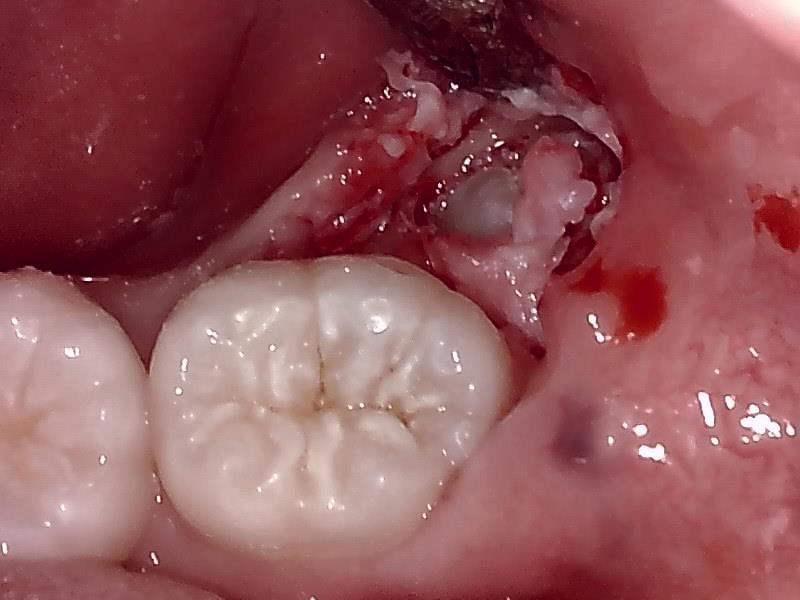

歯牙を分割して抜去する。

侵襲を最小限に軽減して分割して抜去する。

分割して隙間から抜去する。